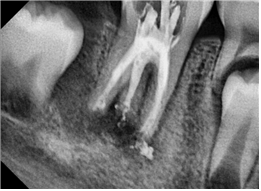

2022. 06. 24 일 파노라마 사진입니다. # 46 치아는 타 치과에서 신경치료 중이라고 합니다.

정말 아쉬운 신경치료 상태인데, 그마저도 치근단 형성이 덜되어 1년 기다렸다 다시 치료를 하자고 했다고 합니다.

치근단유도술을 위해선 저렇게 내부 신경을 다 제거하는 게 아니지만, 제 치료가 아니니 더 설명은 하지 않았습니다.